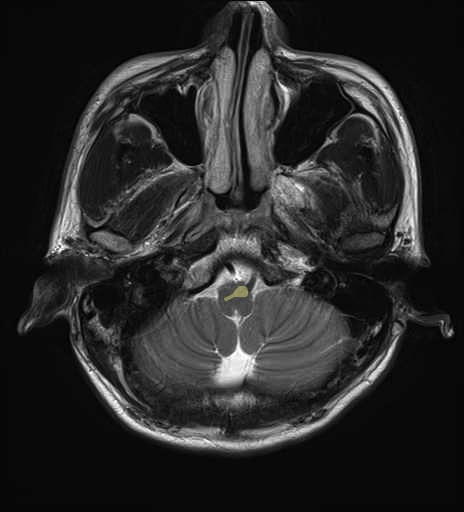

運動系 錐体路系に色を付けました。

■皮質脊髄路(いわゆる錐体路):一次運動野から脊髄遠隔の下位運動ニューロン細胞体まで

■皮質核路:一次運動野から橋及び脊髄神経核まで